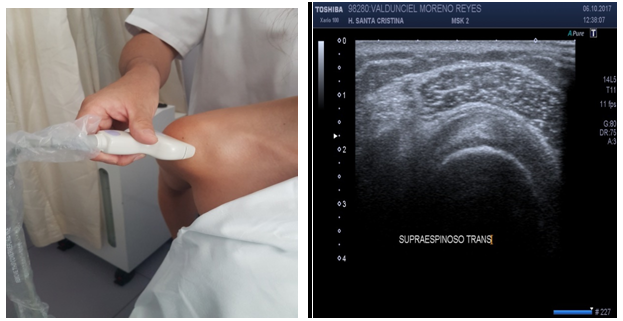

Supraspinatus tendon (long axis) (Figure 7)

Patient position: Patient facing direction of shoulder been studied, 90º to the examiner with hand on back pocket and elbow tucked in (“Marilyn Monroe position”).

Probe position: Probe on coronal position gives a long axis view.

Scan of structures: Supraspinatus tendon looks like a bird peak. The superficial aspect of the supraspinatus must be convex.

Abnormal findings: If superficial aspect of supraspinatus tendon is concave or “dented”, a tear must be suspected. Hyperechoic (bright) cartilage signal may indicate a tear.17,18

Supraspinatus tendon (short axis) (Figure 8)

Probe position: Probe on sagittal position gives a short axis view. This view is obtained rotating the probe 90º from position.

Scan of structures: Supraspinatus tendon has a convex image like a “tire on a wheel”.

Abnormal findings: A concave image or “flat tire” image may indicate partial tear. A dark line greater than 2mm between supraspinatus and deltoid may denote SASD bursitis.17,18

Figure 1 (A) The position of the shoulder may favor the exposition of anatomical structures. Supraspinatus tendon is better exposed on the “Marilyn Monroe pose”, (B) while supraspinatus tendon is better exposed on the “military position”.

Figure 7 Sonoanatomy of the supraspinatus tendon (short/transverse axis).

Figure 8 Sonoanatomy of the supraspinatus tendon (long axis).